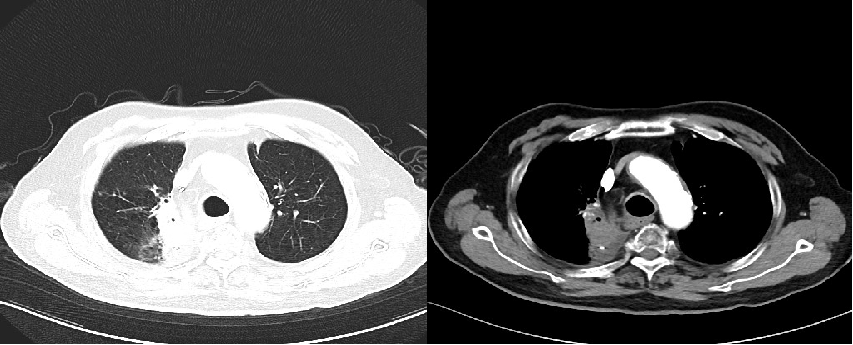

2022-02 胸腹部增强CT(图1):右肺上叶周围型肺癌影像表现,COPD、右肺下叶及左肺上叶纤维灶、结节灶,邻近支气管扩张影像学表现;双侧肾上腺增粗,左侧肾上腺结节灶,符合双侧肾上腺转移瘤影像表现,左肾囊肿。